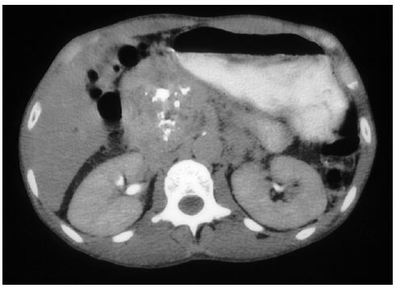

A 22-year-old male presents with his fourth episode of pancreatitis. A computed tomography (CT) scan of the pancreas is shown above. He has two first degree relatives with chronic pancreatitis. There is no other significant family history. The most likely explanation for his episodes is:

Answer

• A. cystic fibrosis.

• B. alcoholic pancreatitis.

• C. hyperparathyroidism.

• D. hereditary pancreatitis.

• E. haemochromatosis.